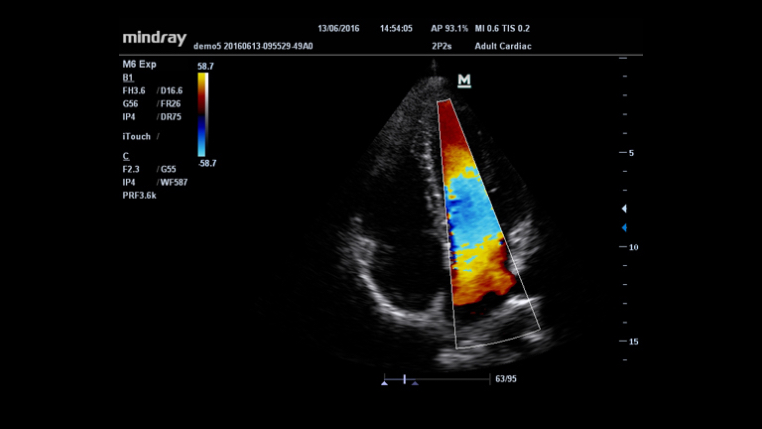

HR Flow?

iTouch? (automatyczna optymalizacja obrazu)

Funkcja ta pozwala uzyska? natychmiastow? automatyczn? optymalizacj? obrazu w trybach B, Kolorowego Dopplera i PW (Spektralnego Dopplera Fali Pulsacyjnej) poprzez naci?ni?cie jednego klawisza.